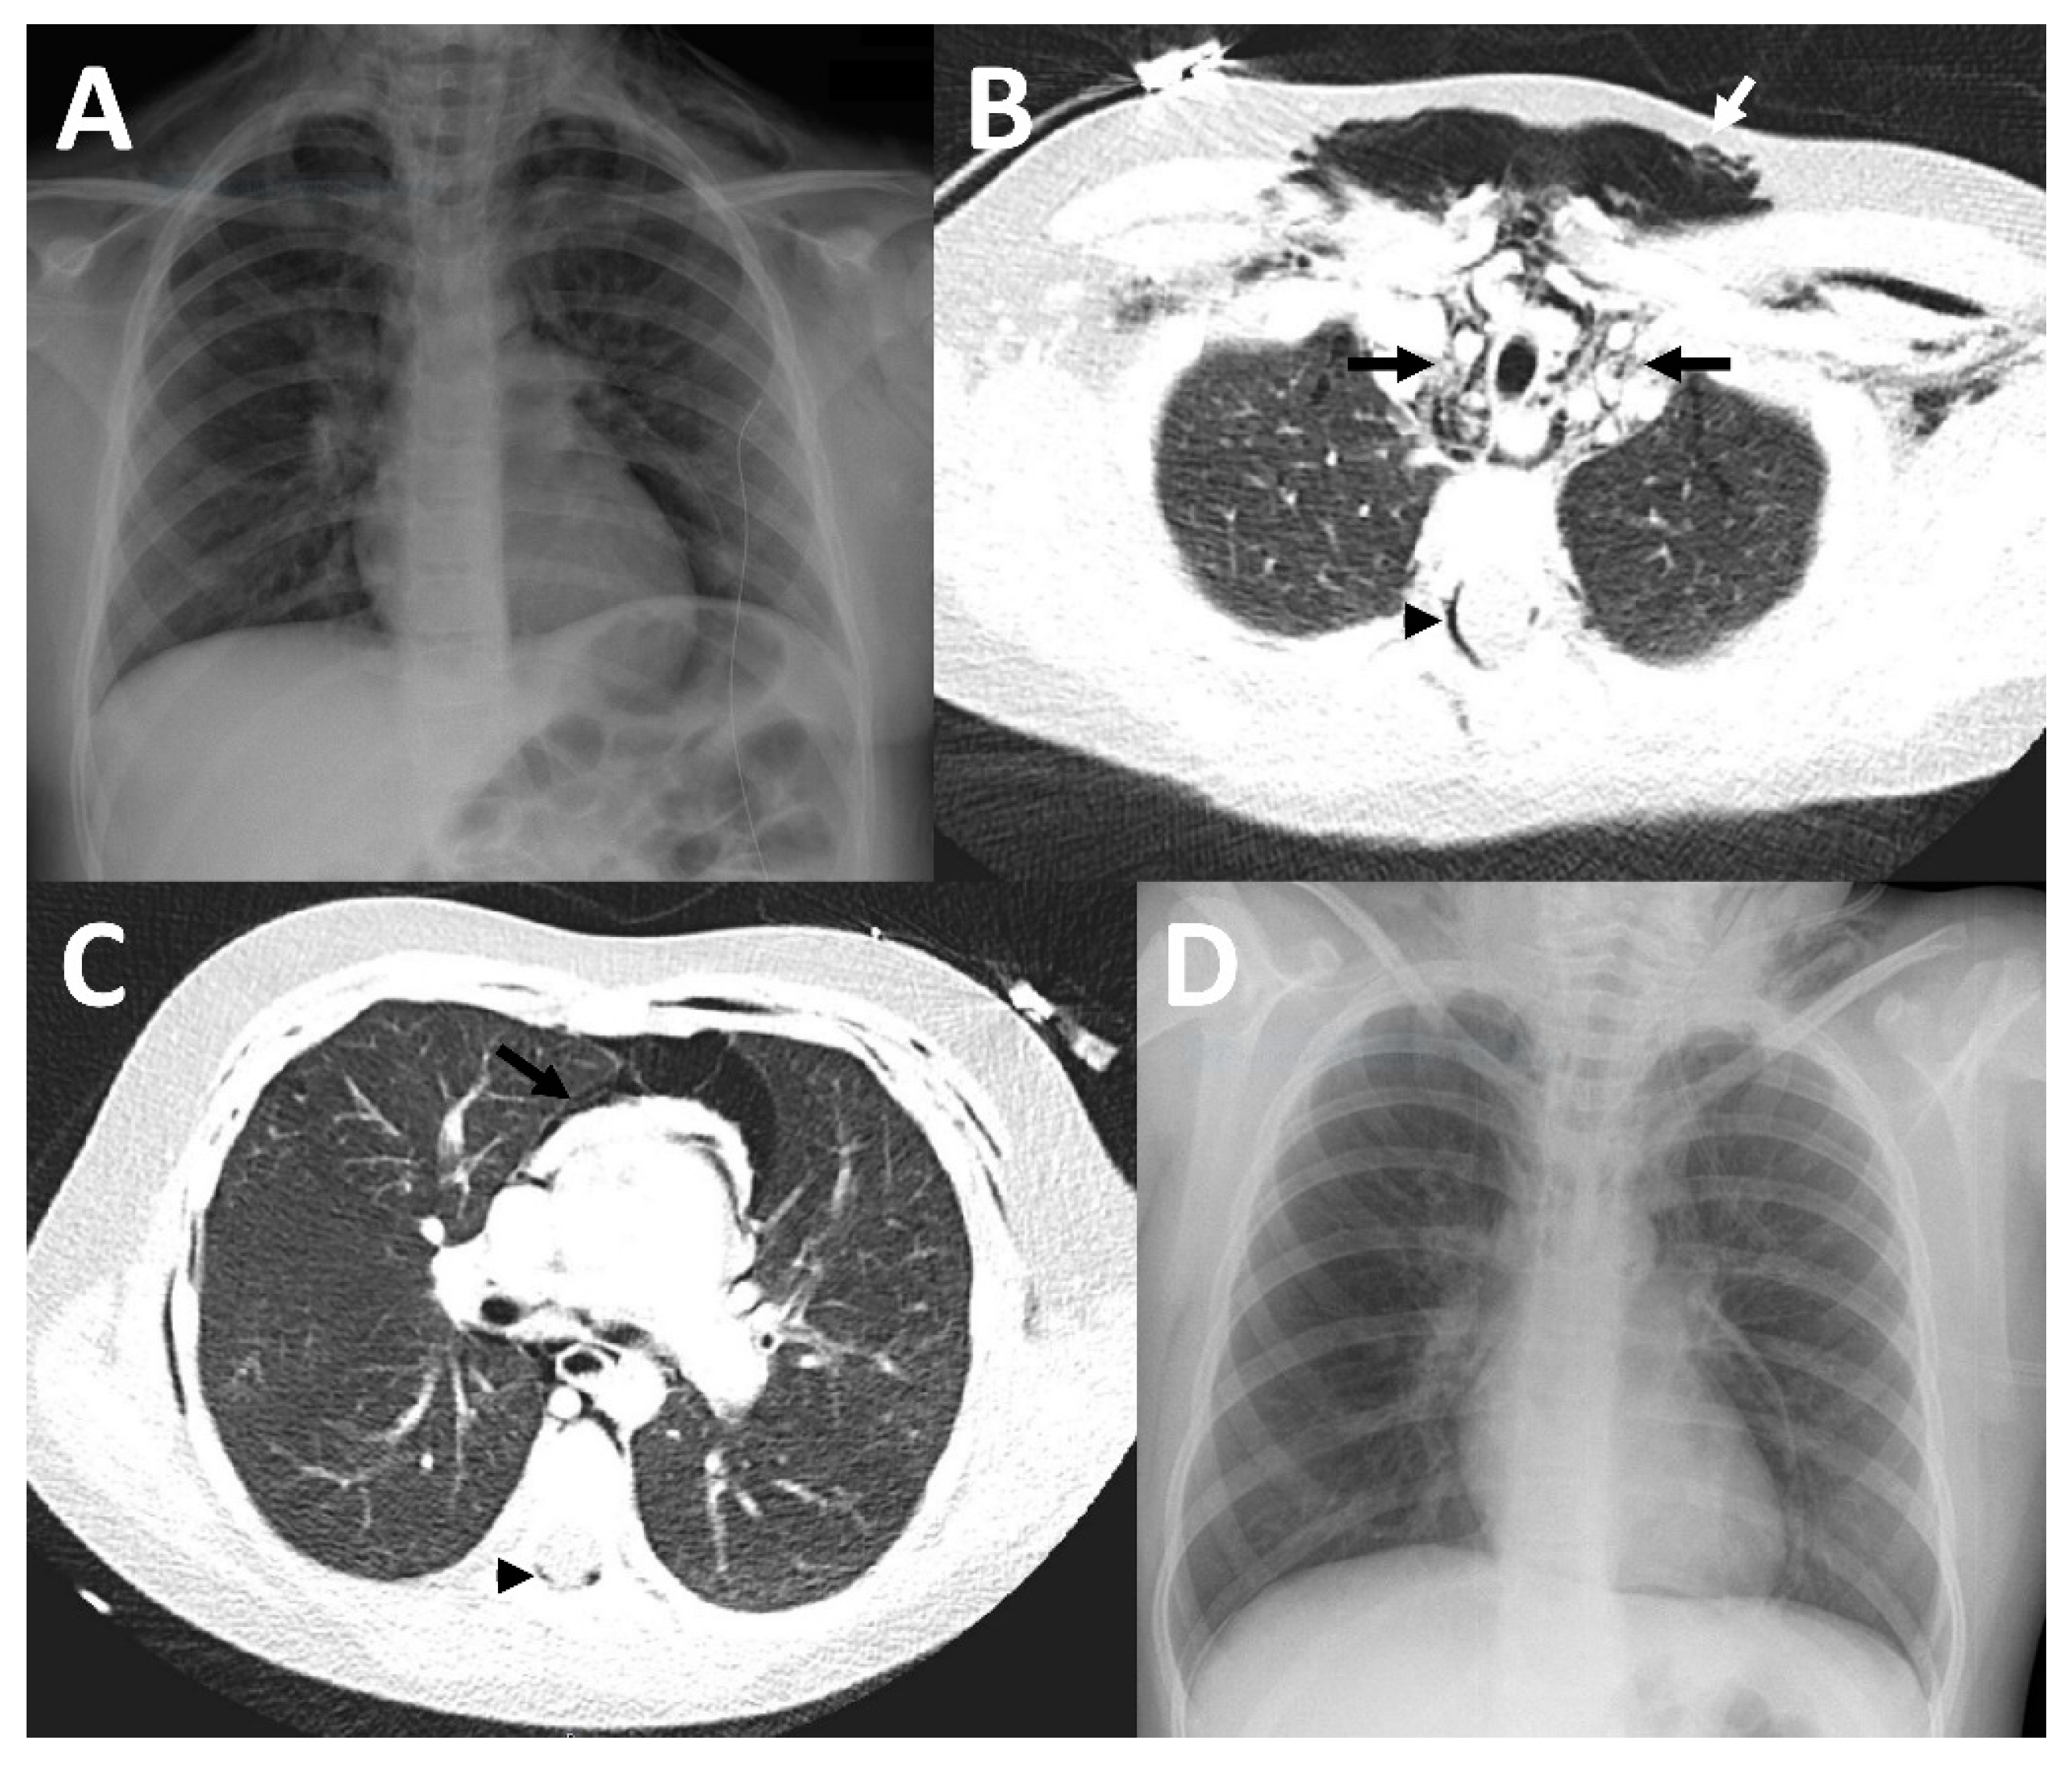

Figure 3.

Imaging findings in patient 3. In the initial chest X-ray, pneumopericardium was suspected (A). Therefore, a CT was performed (B,C) which showed a pneumomediastinum (black arrows), accompanied by a large subcutaneous emphysema (white arrow) and epidural pneumatosis (black arrowhead), but no pneumopericardium. A chest X-ray (D) which was acquired at discharge showed substantial improvement of the previously mentioned findings.